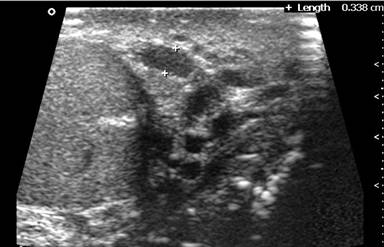

A chronic alcoholic 29-year-old male presented with complaints of heaviness in the scrotum since a few days and lumpish feel in the abdomen since a few weeks. Sonography scrotum revealed multiple dilated, tortuous serpiginous anechoic channels situated on the posterolateral aspect of the left testis (Image 1).These channels were venous in nature and had continuous reversal of flow on Valsalva maneuver. The right testis was normal. On abdominal sonography, there was a 20x12x18 cm huge cystic lesion present predominantly in the epigastrium and left hypochondrium. A CT was performed which confirmed the findings. Besides, there was dilation of the pancreatic duct with calcification in the pancreatic head. The cystic lesion was a huge pseudocyst in the setting of chronic calcific pancreatitis. The pseudocyst was seen to compress the left renal and testicular veins with consequent secondary varicocele on left. There was rightward displacement of the aorta (Image 2: a) and inferior vena cava (Image 2: I). CT in venous phase with coronal reconstruction depicts the huge pseudocyst centered predominantly in epigastrium and left hypochondrium. There is prominence of testicular venous plexus on left (Videoclip). The serum lipase and amylase levels were 501 U/L (reference range: 40-290 U/L) and 1,024 IU/L (reference range: 25-125 IU/L), respectively. A cystogastrostomy was performed which lead to decompression of both the pseudocyst and the varicocele.

Image 1 |